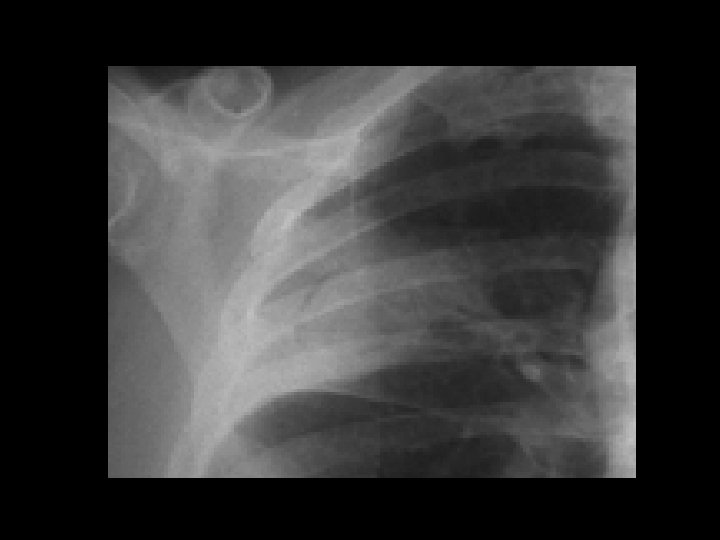

Left hydropneumothorax • Findings: – left pnuemothorax – left pleural effusion (possibly blood) • causes: – penetrating trauma – iatrogenic – bronchopleural fistula